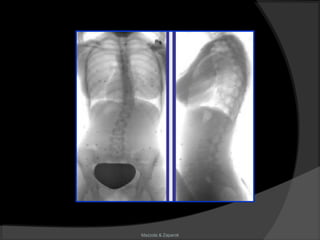

Escoliose

Mazzola & Zaparoli

Definição

“É uma deformidade ântero-posterior em

lordose, causada por um movimento em

torção de todo segmento raquidiano. Essa

deformidade se expressa lateralmente e

trata-se de uma curva reversa.”

(Perdriolle)

Aspectos radiológicos

 Topografia;

 Ângulo de Cobb;

 Rotação:

Nash-Moe

Perdriolle

 Bending – test;